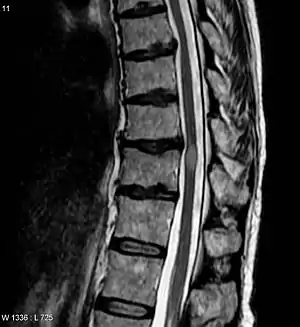

Myelitis has an extensive differential diagnosis. The type of onset (acute versus subacute/chronic) along with associated symptoms such as the presence of pain, constitutional symptoms that encompass fever, malaise, weight loss or a cutaneous rash may help identify the cause of myelitis. In order to establish a diagnosis of myelitis, one has to localize the spinal cord level, and exclude cerebral and neuromuscular diseases. Also a detailed medical history, a careful neurologic examination, and imaging studies using magnetic resonance imaging (MRI) are needed. In respect to the cause of the process, further work-up would help identify the cause and guide treatment. Full spine MRI is warranted, especially with acute onset myelitis, to evaluate for structural lesions that may require surgical intervention, or disseminated disease.[11] Adding gadolinium further increases diagnostic sensitivity. A brain MRI may be needed to identify the extent of central nervous system (CNS) involvement. Lumbar puncture is important for the diagnosis of acute myelitis when a tumoral process, inflammatory or infectious cause are suspected, or the MRI is normal or non-specific. Complementary blood tests are also of value in establishing a firm diagnosis. Rarely, a biopsy of a mass lesion may become necessary when the cause is uncertain. However, in 15–30% of people with subacute or chronic myelitis, a clear cause is never uncovered.[9]